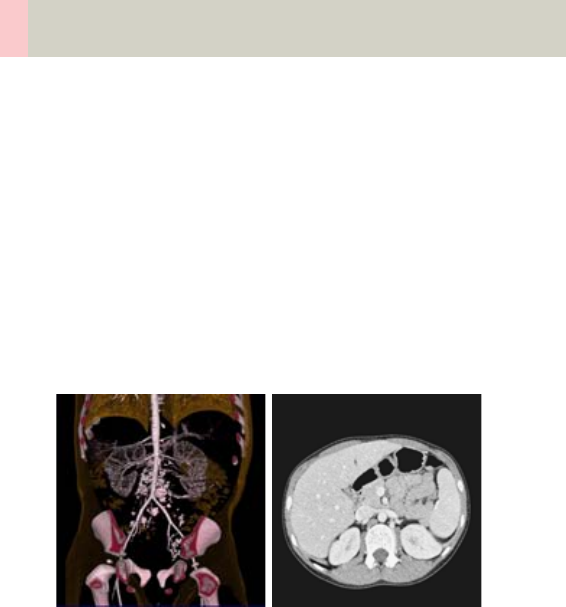

Vascular 360

•Overview 360

- General Hints 363

- Head Kernels 364

- Body Kernels 365

•Scan Protocols 366

- BodyAngioRoutine/

BodyAngioRoutine06s 398

- BodyAngioVol 402